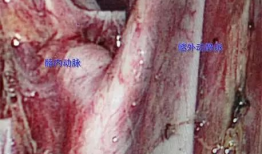

最近网上可是热闹非凡啊!解剖吃瓜事件图片大全,这名字听起来就让人忍不住想一探究竟。这不,我就迫不及待地来给你揭秘这个神秘的世界了...